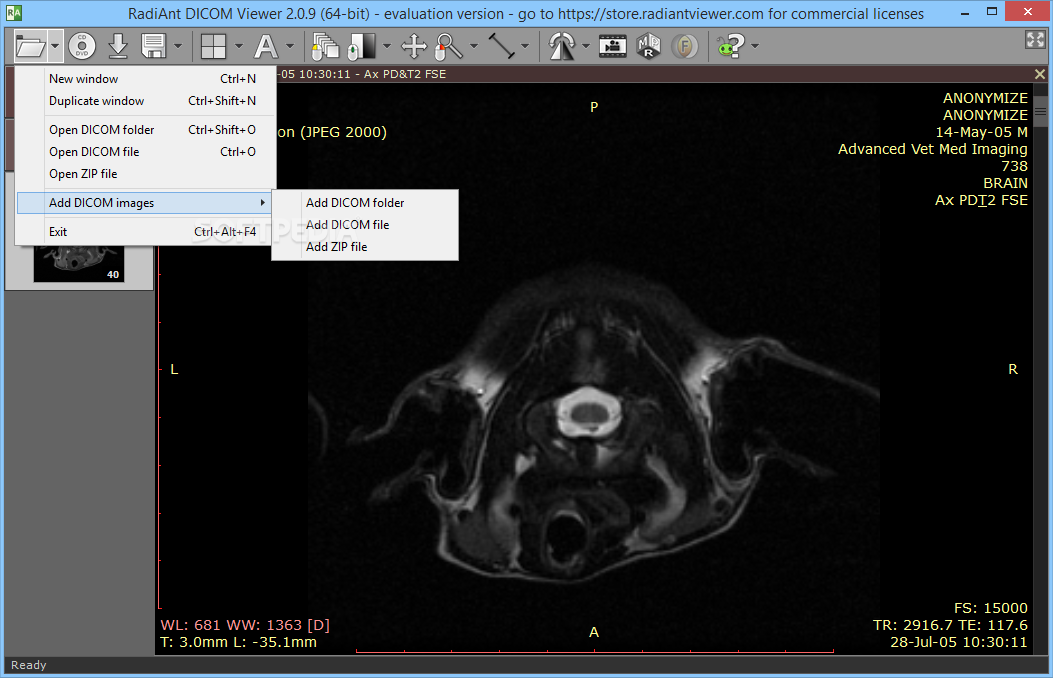

Лазерная камера сетевая для печати изображений на пленке стандарт dicom